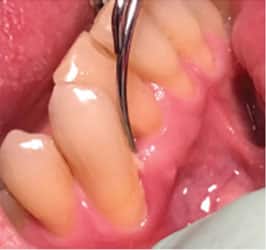

The presence of localized gingival inflammation, triggered by deposit reaccumulation and host response, indicates a need for site-specific debridement. In these areas, place the active tip of a curved UIT at the epithelial attachment and debride with oblique strokes toward the gingival margin (Figure 1). This method of removing lighter deposits supports the use of the side of the active tip instead of the point. Moving from the gingival margin apically encourages using the point on the root or the epithelial attachment, both of which should be avoided unless heavier calculus is being removed or narrow pocketing exists.